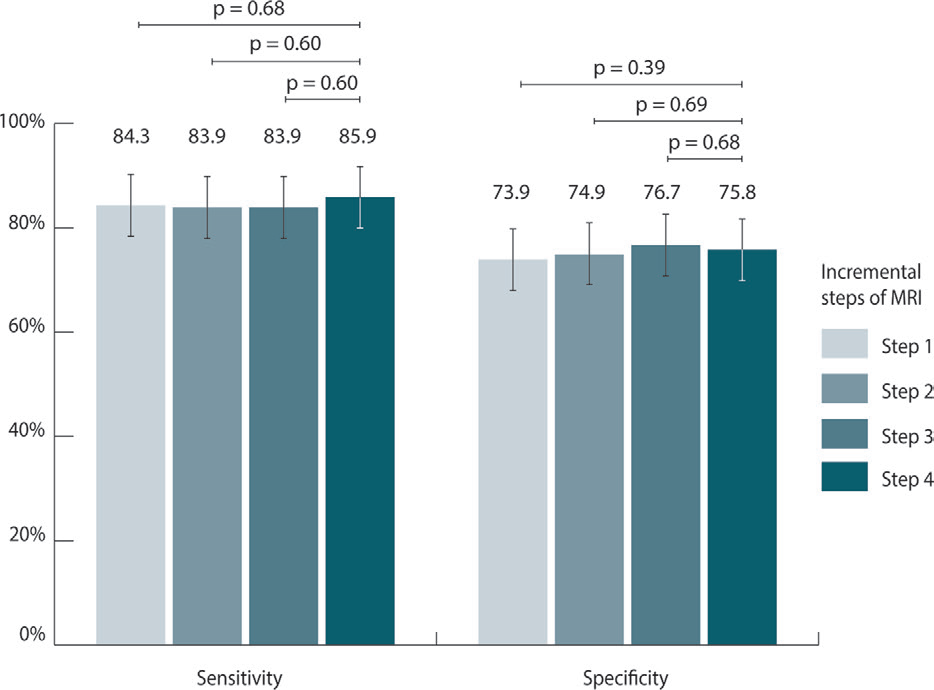

1. 诊断准确性:极简协议 vs 全参数协议

| 指标 | Step 1(极简) | Step 4(全参数) | P 值 |

|---|---|---|---|

| 敏感性 | 84.3%(95%CI:77.7-89.2) | 85.9%(95%CI:80.0-90.3) | 0.68 |

| 特异性 | 73.9%(95%CI:70.7-76.9) | 75.8%(95%CI:72.8-78.5) | 0.39 |

| 浸润性癌敏感性 | 87.3%(95%CI:80.7-91.8) | 88.3%(95%CI:82.3-92.4) | 0.78 |

关键发现:仅保留对比剂注射后 120 秒内的动态 T1 序列,即可捕捉 84.3% 的乳腺癌,与全参数协议无统计学差异。